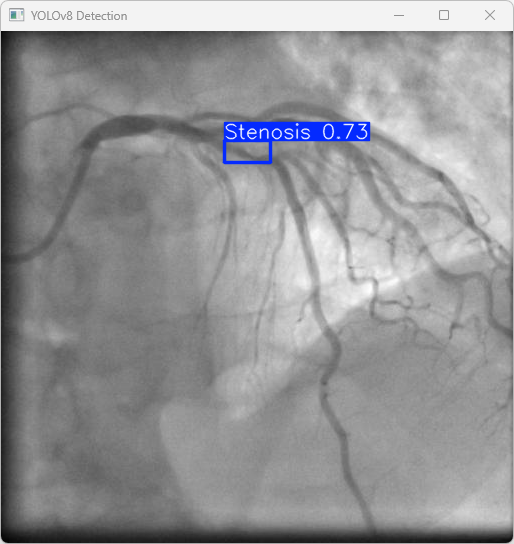

4.检测结果识别

模型训练完成后,我们可以得到一个最佳的训练结果模型best.pt文件,在runs/train/weights目录下。我们可以使用该文件进行后续的推理检测。

imgTest.py 图片检测代码如下:

执行imgTest.py代码后,会将执行的结果直接标注在图片上,结果如下:

这段输出是基于YOLOv8模型对图片“imagetest.jpg”进行检测的结果,具体内容如下:

图像信息:

(1)处理的图像路径为:TestFiles/imagetest.jpg。

(2)图像尺寸为640×640像素。

检测结果:

(1)模型在图片中检测到:1 个Stenosis(狭窄性血管病变)。

处理速度:

(1)预处理时间: 5.0 毫秒

(2)推理时间: 6.2 毫秒

(3)后处理时间: 98.6毫秒

总结:

YOLOv8模型成功检测出1个狭窄性血管目标,推理速度高效,结果保存在指定目录,可进一步优化后处理速度和泛化性能。